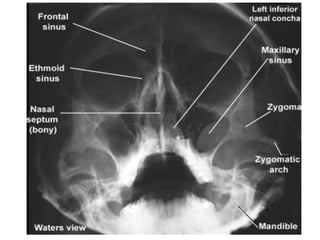

1. Occipito-Mental OM (Water’s view).

1. Occipito-mental OM (Waters view).

• The patient faces the skull table/x-ray couch, with the

chin (usually also the nose) in contact with it so that the

RBL is at 45° to the vertical.

• Centre; To the lower orbital margin.